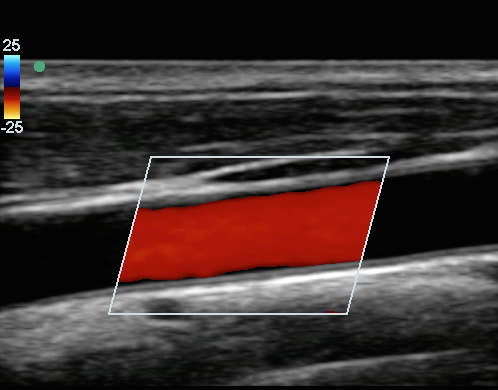

頸動脈の一般的な頚動脈 (CCA) カラー画像